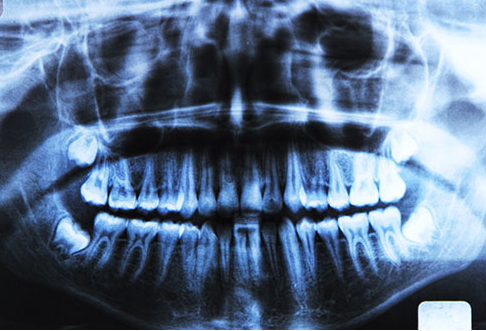

Các nghiên cứu đã chỉ ra rằng không có mối liên quan giữa những chất hàn có chứa thủy ngân và ung thư hoặc bất kì bệnh lí nào khác. Vì vậy, đừng vội vàng đến nha sĩ để gỡ bỏ hoặc thay thế chúng.